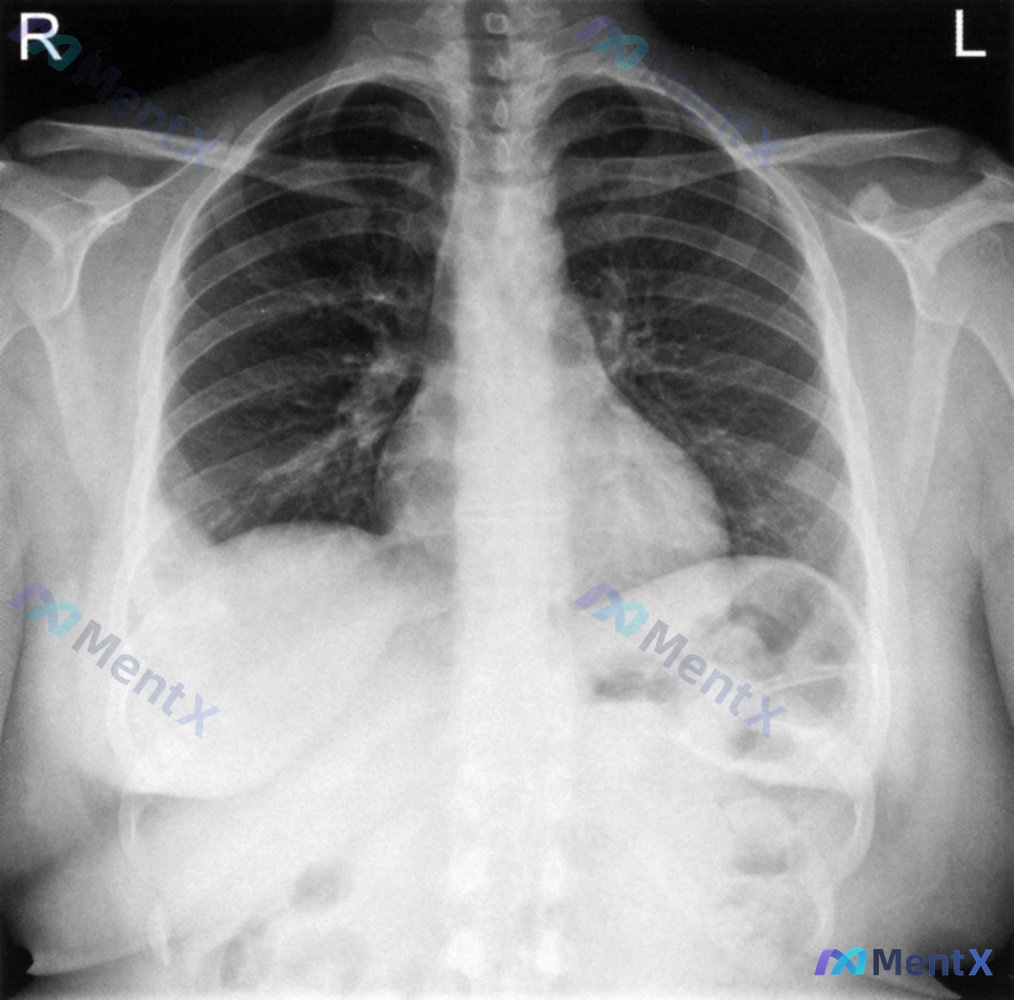

影像资料(胸部X光正位)

影像报告的描述是:

右侧横膈上方明显半圆形高密度影,膈肌局限性抬高,边缘光滑,考虑“膈肌隆起/膈上肿块”;余肺野、心影、纵隔未见明确异常。

- 胸片的“右膈上方半圆形高密度影”——换个角度看,这不就是Hampton驼峰吗!(基底位于胸膜的楔形/半圆形影,是肺梗死的典型X线征象,有时候会被误读为“膈肌抬高”);

关于影像的误读再补充一句:Hampton驼峰其实不是“真的膈肌抬高”,而是肺梗死的高密度影刚好贴在横膈上方,边缘又比较光滑,所以看起来像是膈肌往上拱了一块——如果仔细看侧位片(虽然这个病例没给),可能会发现这个影是在肺实质内,而不是膈肌本身。